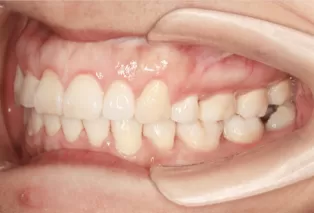

Photos intra-orales